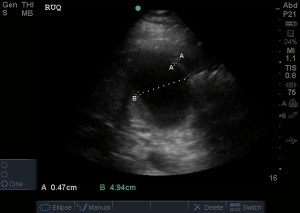

Gallbladder: transverse:

Gallbladder: Long:

The normal gallbladder measurements are an anterior gallbladder wall of 3mm, a width of 4cm and a length of no more than 9-10cm. The common bole duct (not measured) should be 6mm at the age of 60yrs (adding a mm for every decade above 60). The above image also shows a small amount of sludge but no obvious gallstone (it may have went into the bile duct and obstructed there). So, putting it together – this is obviously abnormal and evidence of acute cholecystitis.